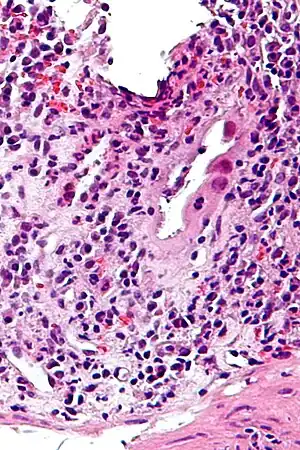

| Micrograph of CMV colitis. H&E stain. | |

CMV colitis may be clinically manifested with diarrhea (usually non-bloody), abdominal pain, weight loss and anorexia. The diagnosis of CMV colitis is based on serology, CMV antigen testing and colonoscopy with biopsy. Clinical suspicion should be aroused in the setting of immunocompromised patient but it is much rarer in immunocompetent patient. Although it is known that CMV colitis is almost always caused by reactivation of latent CMV infection in immunocompromised patients, new infection of CMV or reinfection of different strain of CMV can cause colitis in immunocompetent hosts. Because asymptomatic CMV viremia and viruria is common and about 1/3 of symptomatic CMV infection is caused by reinfection of different strain of CMV, the diagnosis of CMV colitis needs more direct causality. It is practically achieved by colonoscopy or sigmoidoscopy tissue sampling and pathological evidence of CMV infection under microscope, more specifically macroscopic picture will show many ulcers that appear on the mucous membrane and microscopically the biopsy will show intranuclear and cytoplasmic inclusion bodies. Positive CMV IgG doesn't necessarily mean that it is reactivation of latent infection because of the possibility of reinfection of different strain.